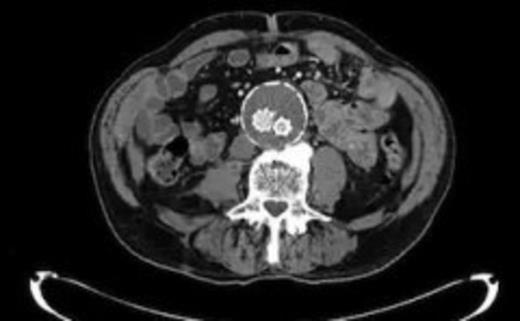

Four weeks following discharge the patient was re-admitted with feeling increasingly unwell, recurrent pyrexia, loss of appetite and mild shortness of breath on exertion. Physical examination was unremarkable except for a temperature of 38.3 centigrade. Blood tests on admission showed Hb 11.4 g/dl (11.5-16.0 g/dl), white cell count 13.1×109/L (4-9.2 x 109/L) and CRP 68mg/L (<3 mg/L). Contrast enhanced CT scan (Fig. 2,3) showed a 50 mm maximum retroperitoneal collection situated between the right kidney and the right iliac vessels. It contained a few loculi of gas. A diagnosis of postoperative right psoas abscess was made. The patient was started on intravenous broad spectrum antibiotics – Tazocin (Piperacillin+ Tazobactam) and Metronidazole. CT guided drainage was carried out using a 10 French gauge pigtail catheter locked pigtail (Meditech Flexima regular all-purpose drainage catheter sets with locking pigtail (Boston Scientific)) (Fig. 4). The isolation of E. coli from the collection with negative Hemocultures suggested a bowel source for the infection but no actual breach was demonstrable. The bowel surgeons ruled out colonic pathology.

CT guided drainage was carried out using a 10 French gauge pigtail catheter locked pigtail (Meditech Flexima regular all-purpose drainage catheter sets with locking pigtail (Boston Scientific))